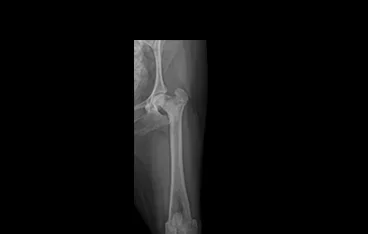

• PLATE 수술 전

PLATE 수술 후